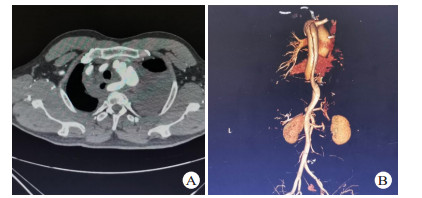

2 结果13患者接受TEVAR。11例夹层破口位于胸降主动脉峡部,2例夹层破口位于降主动脉中段; 累及左侧锁骨下动脉2例,左侧锁骨下动脉开口周围血肿1例; 合并迷走右锁骨下动脉1例(图 3)。破口距离左侧锁骨下动脉开口距离0~51 mm,(30.14±14.85)mm,累及左侧锁骨下动脉2例及左侧锁骨下动脉开口血肿1例患者完全覆盖左侧锁骨下动脉; 2例患者因破口距左锁骨下动脉开口距离近,锚定区不足,覆盖1/2左锁骨下动脉; 1例患者因合夹层累计左侧锁骨下动脉且合并迷走右锁骨下动脉,在手术室先行左侧颈总动脉-左侧锁骨下动脉、右颈总动脉-右锁骨下动脉转流,然后再到介入室行TEVAR手术并覆盖左侧锁骨下动脉。全组主动脉内径27~35 mm,(32.1±3.7)mm,所选择支架直径比CT所测锚定区直径大15%。TEVAR手术时间55~ 129 min,(83.2±21.3)min。本组手术患者死亡1例,病死率为7.7%,死亡原因为合并多根多处肋骨骨折所致呼吸衰竭,1例患者术中造影发现I型内漏,采用高压球囊扩张后内漏消失,其余患者经过治疗后均痊愈出院,住院时间(13.8±6.9)d。出院后失访1例,其余患者均随访1~4年,无支架移位、内漏、截瘫、缺血性脑卒中、左上肢缺血及新发夹层或动脉瘤等并发症,均恢复正常生活。

| 图 3 患者56岁,因车祸伤入院,入院后诊断TAD合并迷走右锁骨下动脉(A:胸部增强CT提示降主动夹层,右侧锁骨下动脉起源于降主动脉,沿食管后方走行,左侧胸腔大量血胸,右侧纵隔积血,B:胸腹部CTA提示降主动脉夹层,夹层累及迷走右锁骨下动脉) |